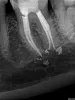

К сожалению, данные опасения вполне оправданы. На данном рентгенологическом снимке наблюдается выход пломбировочного материала за пределы канала зуба. Пломбировочный материал за пределами канала может способствовать развитию периодонтита.

Периодонтит — это воспаление связки зуба, удерживающей его в лунке. Кроме того, возможно, в медиальном корне (тот, который ближе к четвертому зубу) имеется незапломбированный канал.